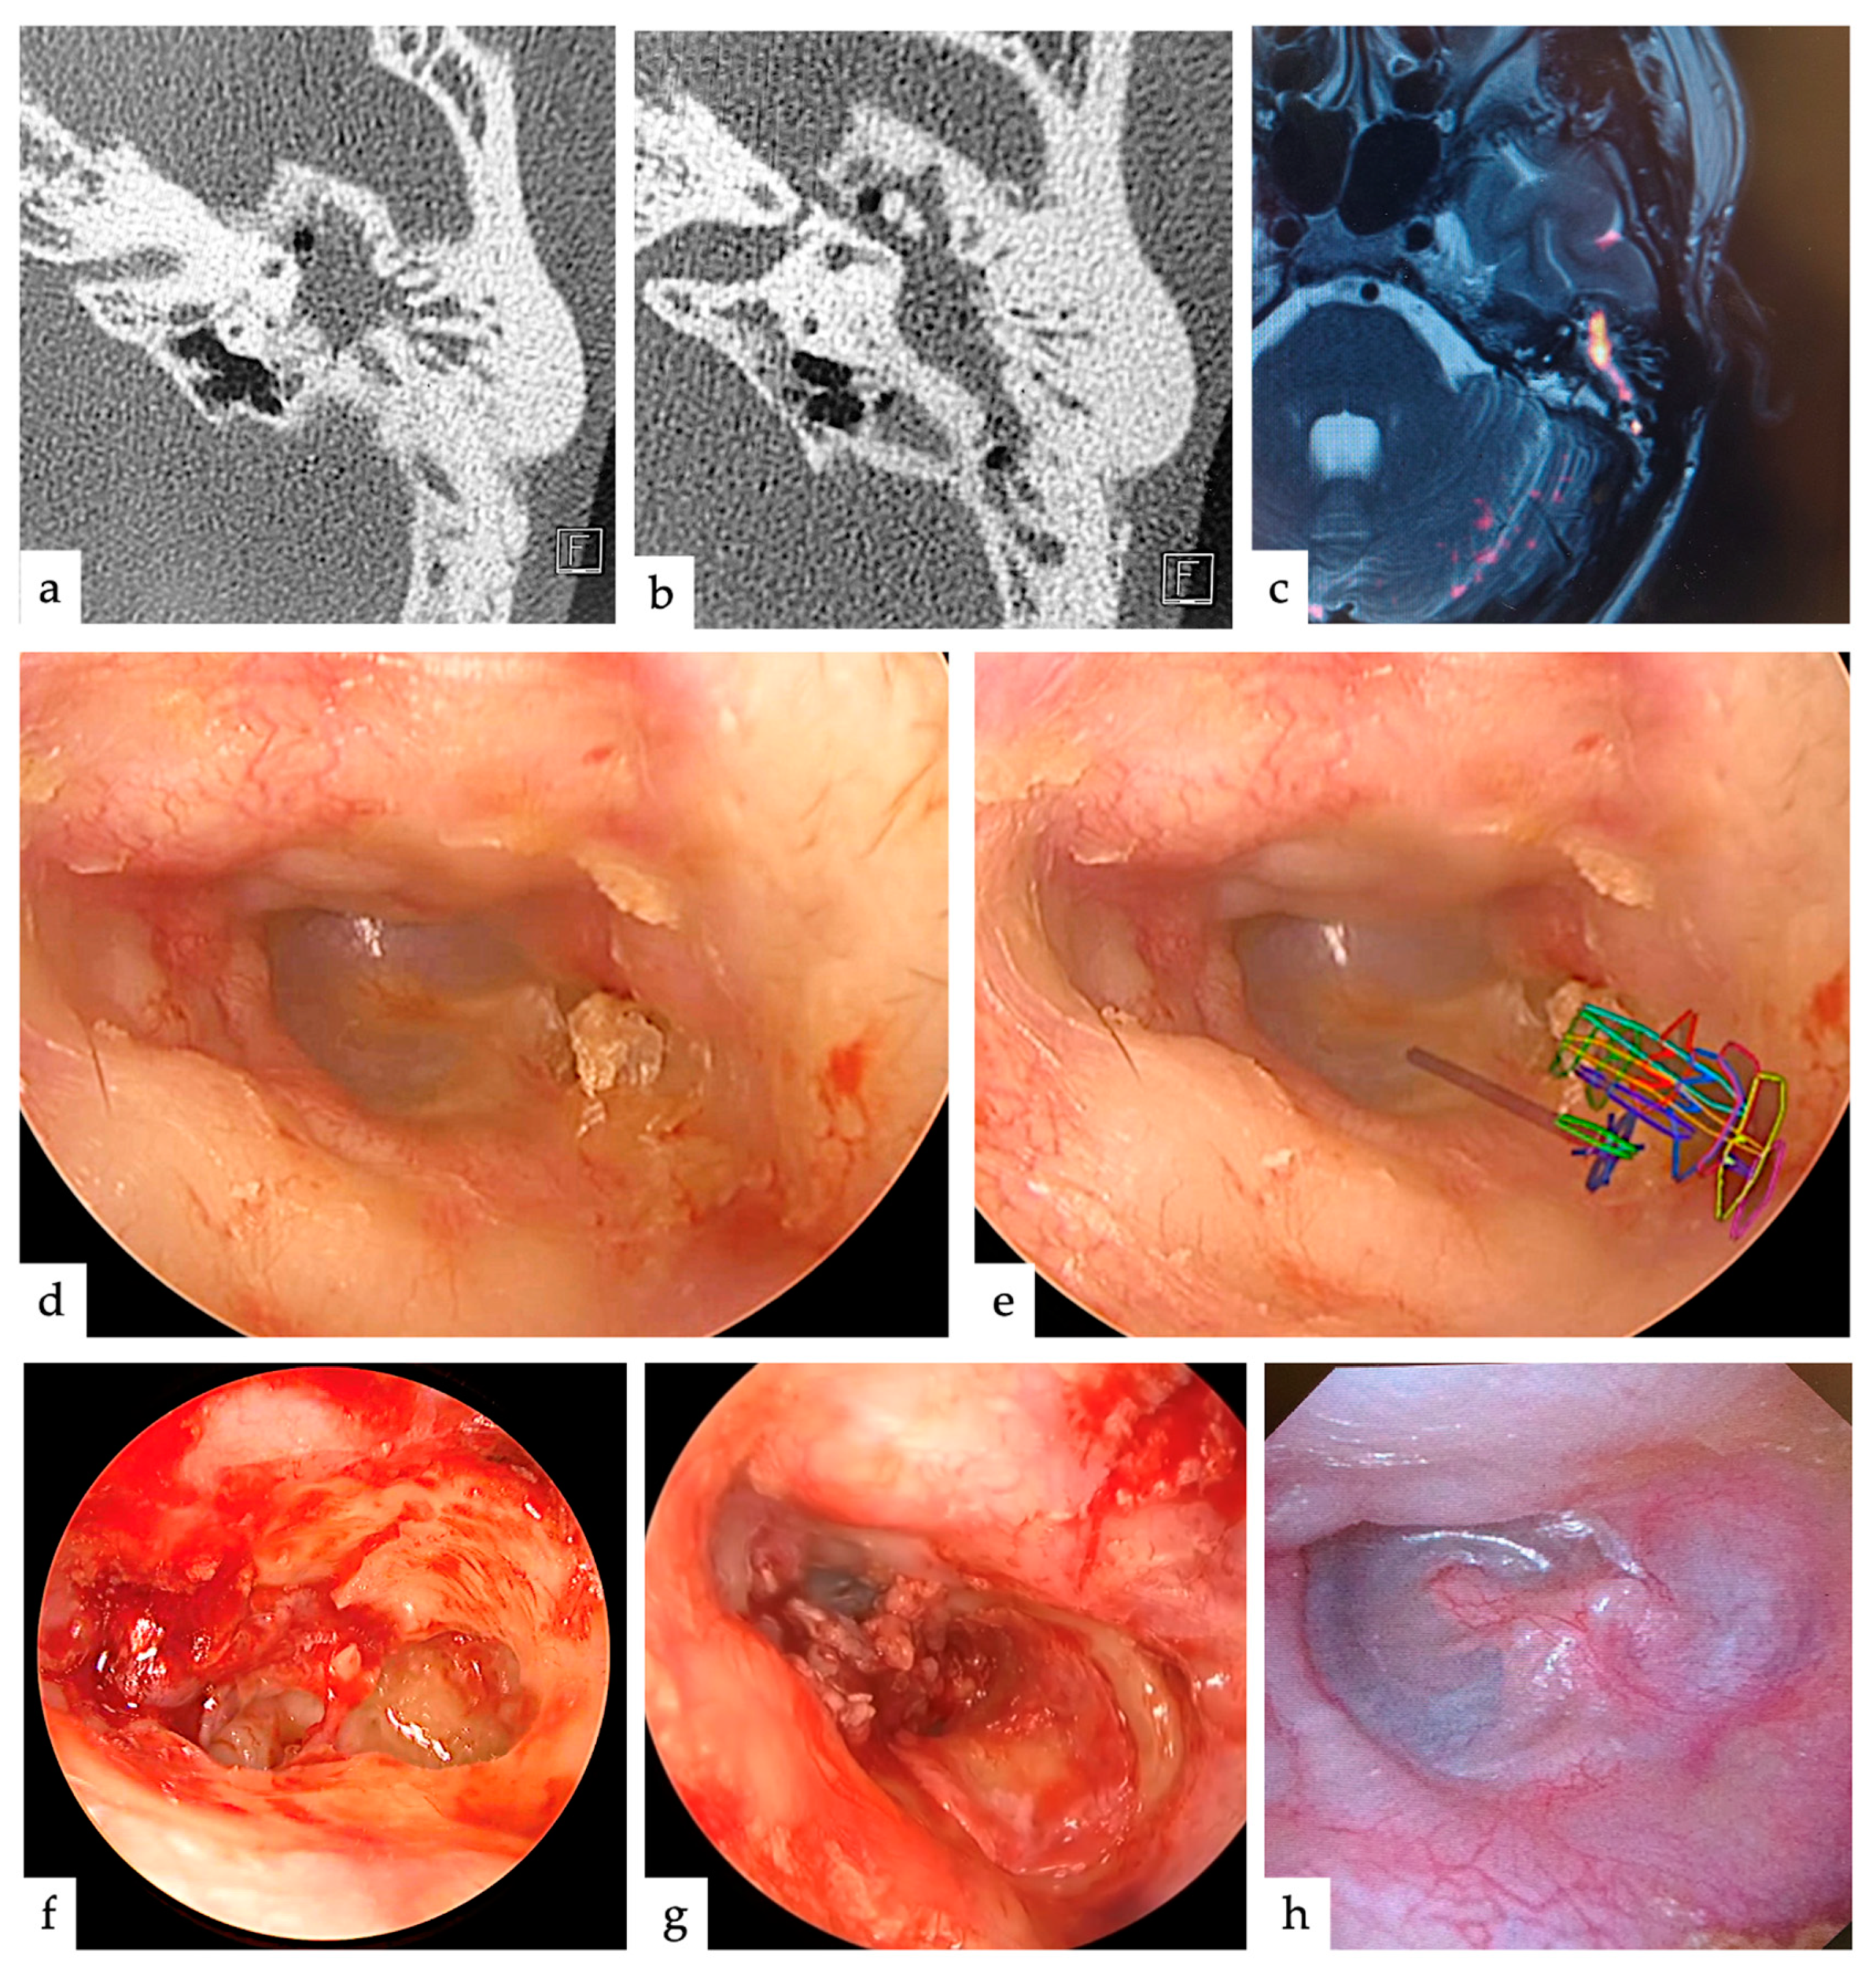

| Case | Age | Sex | Type | Range | TEES/MES |

|---|---|---|---|---|---|

| 1 | 44 | Male | pars flaccida | AM | TEES |

| 2 | 51 | Female | pars flaccida | TAM | MES |

| 3 | 41 | Male | pars flaccida | AM | TEES |

| 4 | 5 | Female | congenital | TAM | TEES |

| 5 | 41 | Male | pars flaccida | AM | TEES |